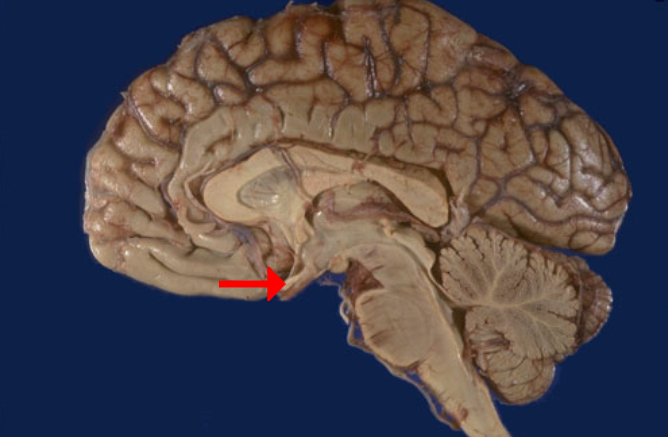

Label this brain part

Thalamus

Label this brain part

Midbrain

Label this brain part

Fourth ventricle

Label this brain part

Medulla

Label this brain part

Corpus callosum

Label this brain part

Mammillary body

Label this brain part

Cerebellum

Label this brain part

Aqueduct of Sylvius

Label this brain part

Tectum (of midbrain)

Label this brain part

Septum pellucidum